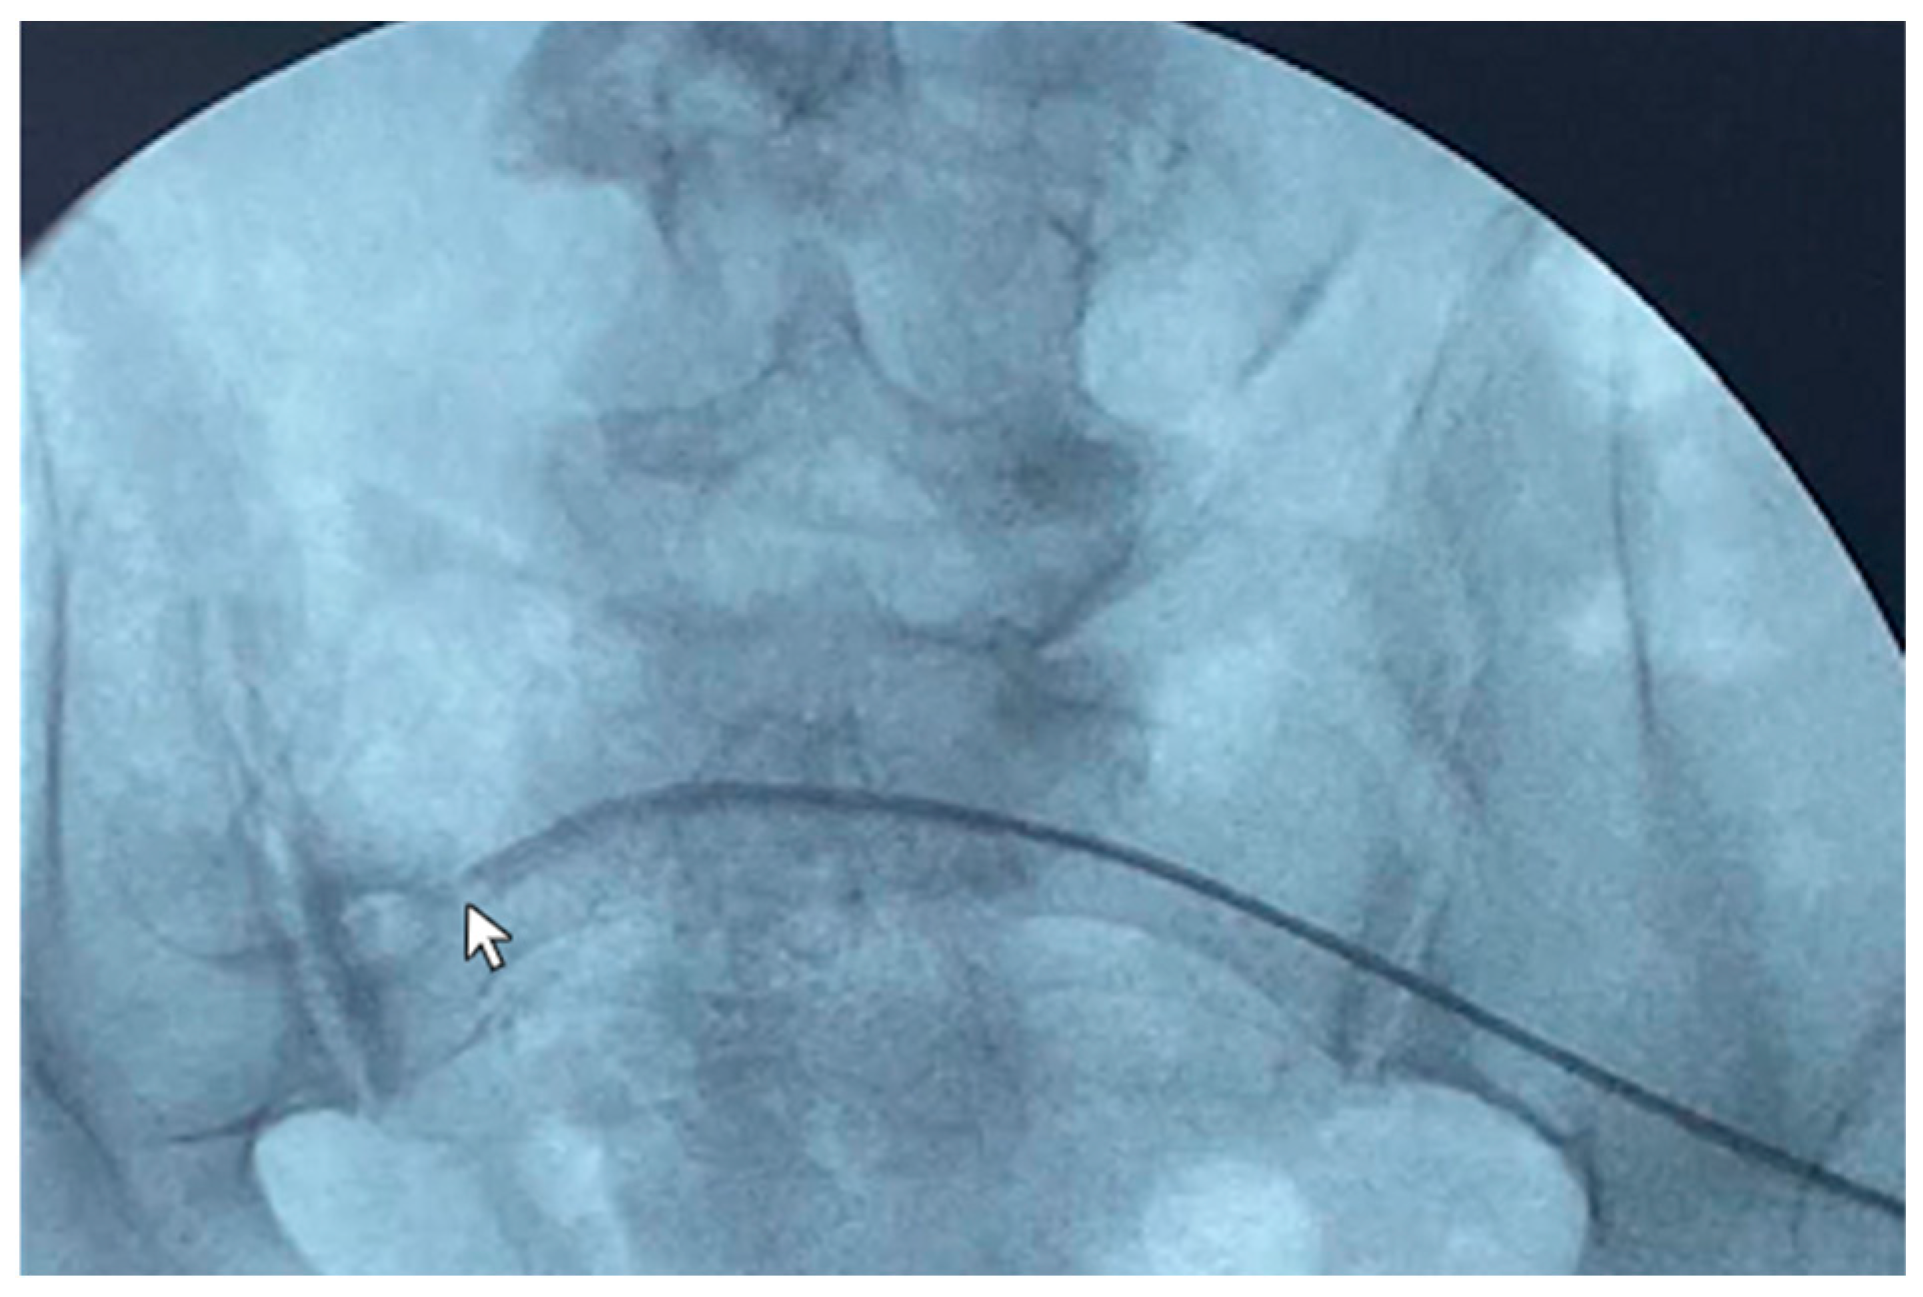

A 48-year-old male patient affected by ADPKD underwent right nephrectomy and concurrently videolaparoscopic peritoneal catheter placement. Two months later, due to persistent abdominal bulk secondary to the contralateral kidney size, the patient underwent a second surgery for left nephrectomy. Three months after the start of peritoneal dialysis, poor inflow and outflow performance was detected with little benefit from laxatives administration. An abdomen X-ray showed the peritoneal catheter rising from the lumbar left region with the tip ending in the lumbar right region (Figure 1).

Figure 1. Catheterography showing the tip (Life 14 01475 i001) of the peritoneal catheter pointing to the lumbar right region. Normal spillage of the contrast medium from the side holes may be seen (Life 14 01475 i002).